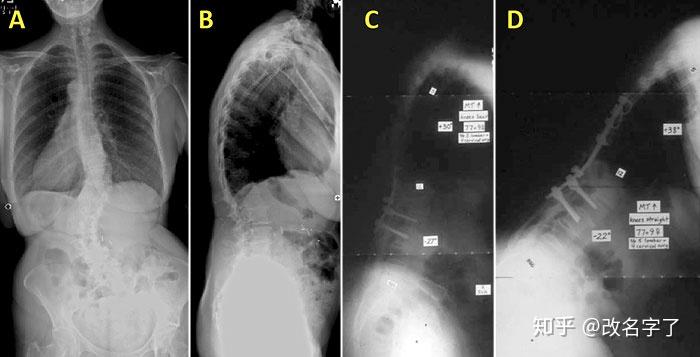

成人特发性脊柱侧弯